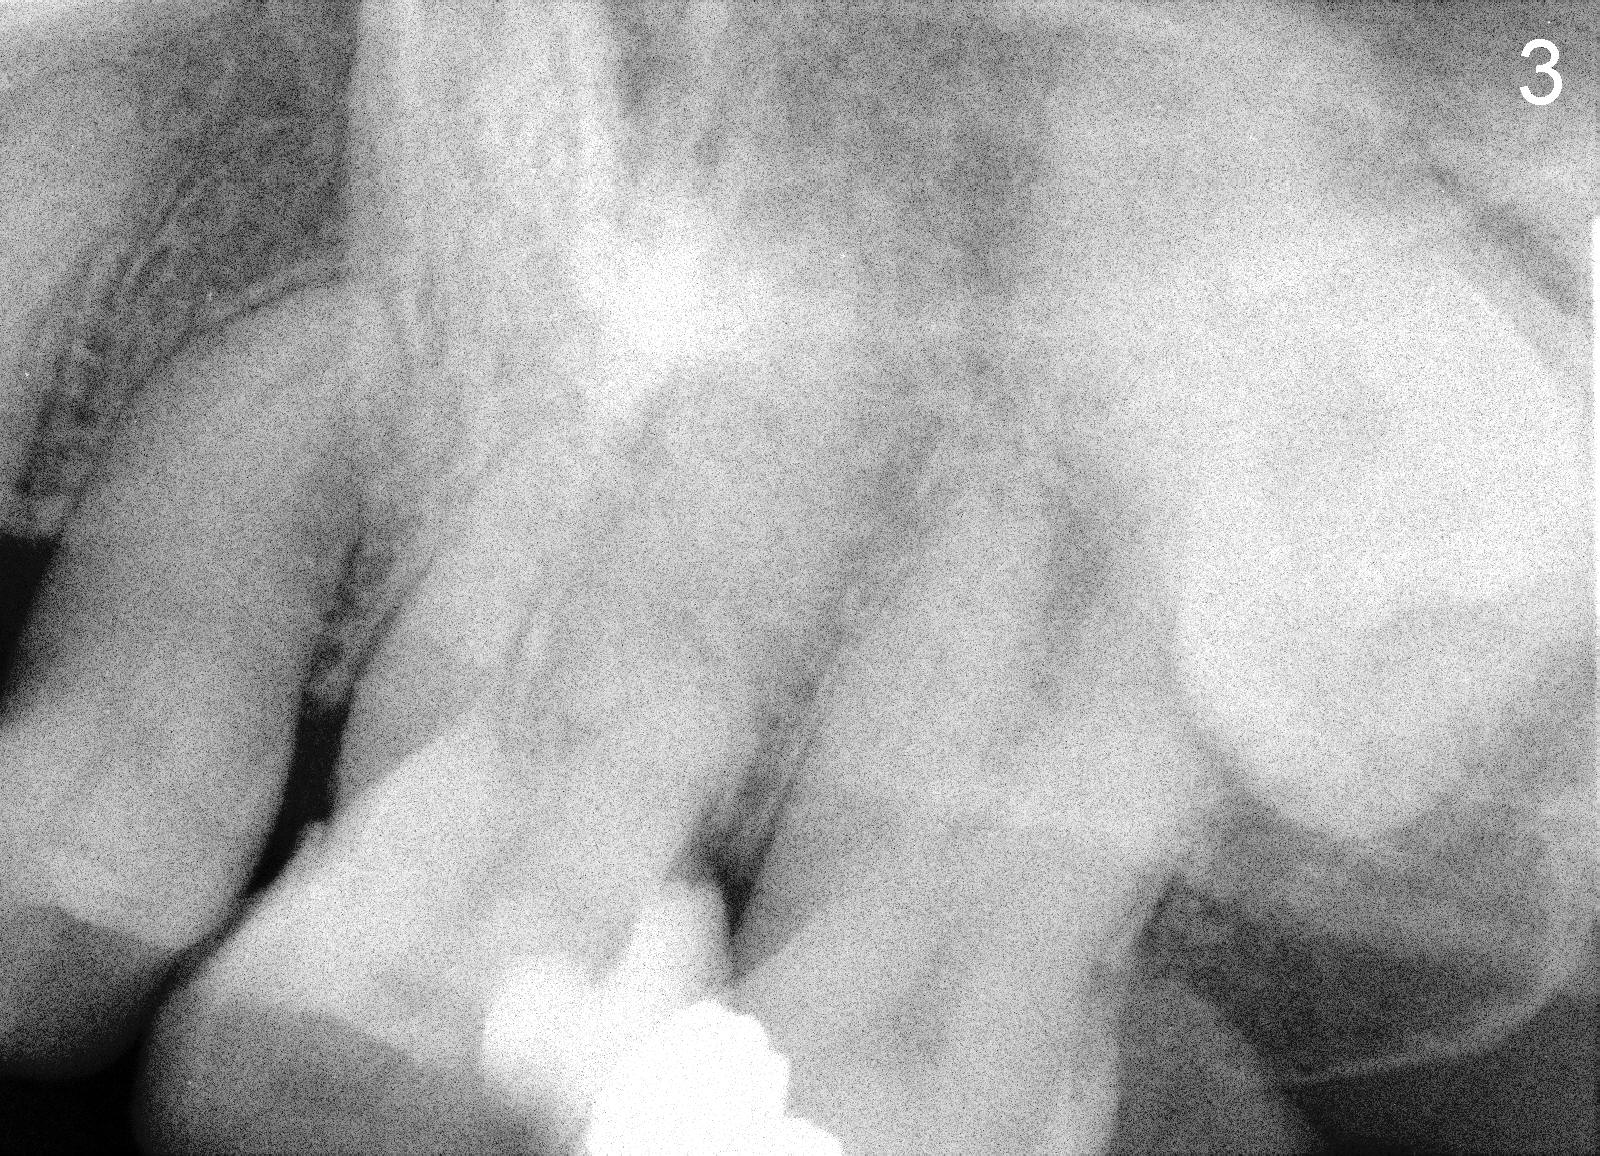

Bitewing and PAs for Upper Left Quadrant

X-ray was taken on 01/18/2010 (Fig.1) and 06/11/2011 (Fig.2-4). Clinically there is no gross lesion in the upper left quadrant, although pain is vague in position, according to the patient.